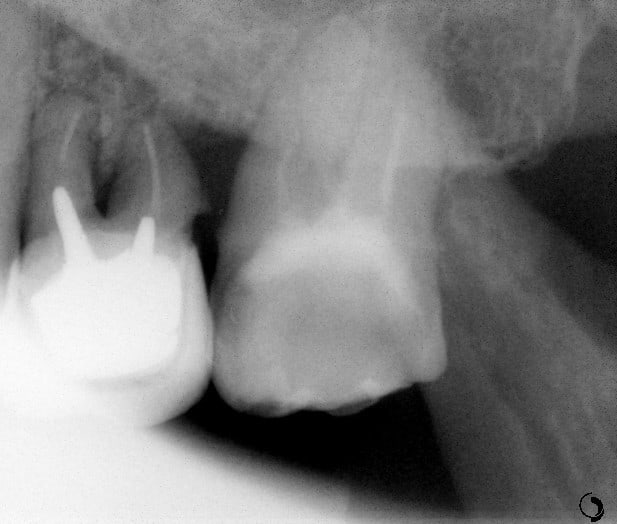

Pour abonder dans le sens qu'il ne faut pas couronner dans tous les cas, voici un cas fait il y a un an.

Les facteurs qui m'ont amené à prendre la décision de faire une endocouronne (proche d'un onlay en vérité) :

- 3 parois solides, la dernière pas trop fine.

- limites toutes supragingivales

- occlusion favorable (pas de photos de l'antagoniste je n'y ai pas pensé)

- patient réceptif

- grande profondeur de la chambre pulpaire (pas très visible sur les photos verticales)

Je n'en fais pas souvent mais quand j'en fait c’est que j'ai confiance. Faire une couronne classique ? Sur ce cas rien que de préparer les limites périphériques et on se retrouve avec une dent à raz la gencive, avec obligation de faire un (ou plusieurs) tenons longs pour une bonne rétention, générateur de fracture radiculaire....

Couronne Emax, collée au Multilink Automix

PS : avant toute remarque, non la patiente ne veut pas que je touche à sa dent de lait résiduelle ;o)

Je me rends compte que la hauteur importante des parois et de la chambres ne sont pas très visibles sur les photos : j’aurais du prendre un angle de biais pour les visualiser en terme photo.